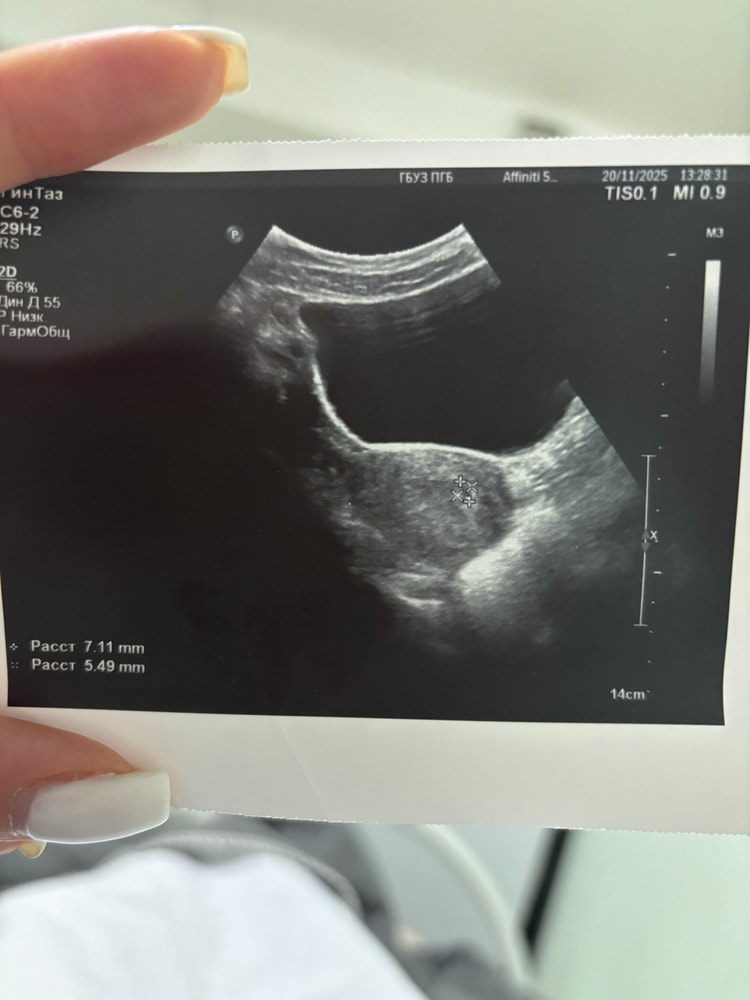

Имплантация в левом трубном углу😐

На 10 дпп начало немного мазать розовым ( выпила транексам и дюны) и решила поехать в больницу. В больнице встретили с распростертыми объятиями ( хотя уже ничего не мазало) но решила полежать. На 15 дпп сделали узи, в проекции левого трубного угла плодное яйцо, заключение: маточная беременность и меня благополучно выписали. Это же не нормально или стоит успокоиться?